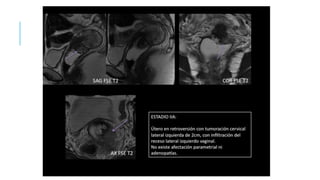

ESTADIFICACION

TC Y RM pudiéndose objetivar la obstrucción ureteral extrínseca, la invasión vesical y rectal,

la presencia de adenopatías y la propagación a nivel extrapélvico. Asu vez, por estos

métodos, pueden monitorearse el tratamiento y la recurrencia del tumor.

Los factores más importantes a tener en cuenta en el informe de los estudios por imágenes

deben incluir:

1) Tamaño del tumor.

2) Profundidad de la invasión miocervical.

3) Grado de extensión de la invasión parametrial (parametrios laterales y uterosacros),

informando si llega hasta la pared pelviana.

4) Presencia de infiltración vaginal.

5) Evaluación de los ganglios linfáticos pelvianos y/o lumboaórticos desde la fosa obturatriz.

6) Evaluación de la infiltración del espacio vésicocérvico- vaginal y/o del espacio recto-vaginal.

7) Evaluación de posibles metástasis a distancia.

ESTADIFICACION TC Y RMpudiéndose objetivar la obstrucción ureteral extrínseca, la invasión vesical y rectal, la presencia de adenopatías y la propagación a nivel extrapélvico. Asu vez, por estos métodos, pueden monitorearse el tratamiento y la recurrencia del tumor. Los factores más importantes a tener en cuenta en el informe de los estudios por imágenes deben incluir: 1) Tamaño del tumor. 2) Profundidad de la invasión miocervical. 3) Grado de extensión de la invasión parametrial (parametrios laterales y uterosacros), informando si llega hasta la pared pelviana. 4) Presencia de infiltración vaginal. 5) Evaluación de los ganglios linfáticos pelvianos y/o lumboaórticos desde la fosa obturatriz. 6) Evaluación de la infiltración del espacio vésicocérvico- vaginal y/o del espacio recto-vaginal. 7) Evaluación de posibles metástasis a distancia.

• #32 La clasificación de las etapas clínicas de la evolución del carcinoma de cuello, partiendo de la etapa cero, que correspondería al carcinoma in situ (CIN-III o HSIL):2 Estadio I: confinado al cuello del útero. Con un estadio IA si el tumor mide menos de 7 mm de superficie y 5 mm de invasión en profundidad; y un estadio IB si el tumor mide más o es macroscópico. Estadio II: se extiende más allá del cuello, pero no se extiende a la pared de la pelvis y, si afecta a la vagina, no llega a su tercio inferior. Se clasifica como IIA si no afecta a parametrios (IIA1 si es menor de 4 cm y IIA2 si es mayor) y IIB si los afecta. Estadio III: el carcinoma se extiende a la pared pelviana. En la exploración al tacto rectal no existe espacio entre el tumor y la pared pelviana; el tumor se extiende además al tercio inferior de la vagina. Sería un estadio IIIA si afecta al tercio inferior de la vagina, y un IIIB si afecta pared pélvica o tiene repercusión sobre el riñón. Estadio IV: estadio metastásico local (puede infiltrar la pared de la vejiga urinaria o el recto) (IVA) o a distancia (IVB), por ejemplo si aparecen en los pulmones.